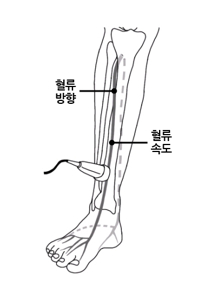

- 혈관 초음파로 혈관 구조를 확인하고 도플러를 통해 혈액의 흐름 방향, 속도, 역류 여부 및 역류 시간을 측정합니다.

- 혈관 내 혈류의 방향, 속도, 역류 여부와 역류 시간을 직접 측정할 수 있습니다.